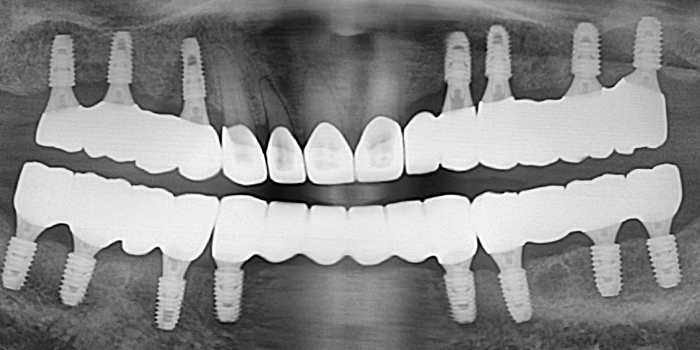

05 60대 남성, 기존 임플란트 부작용으로 재수술, 치료기간 6개월